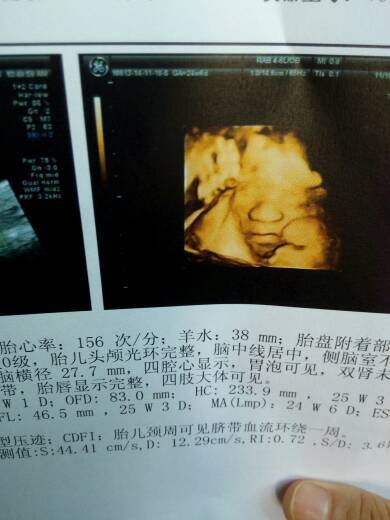

今天老婆照4维了…宝宝大鼻子大嘴巴像老公!谁看的懂是男宝宝女宝宝呀 今天老婆照4维了…宝宝大鼻子大嘴巴像老公!谁看的懂是男宝宝女宝宝呀 点击展开 可可CoCo 2014-11-18 21:25 为您推荐: 其他回答 看胎心150次/分以上是女宝。以下是男宝。 An娜 2014-11-19 10:59 看不懂啊, 雅萌宝宝 2014-11-18 22:39 给你做四维的人知道的。 方小宝 2014-11-18 22:15 看不出来的 冀晴阳妈 2014-11-18 21:35 这个看不出来 俏太太 2014-11-18 21:28 加载更多 相关问题 今天老婆照4维了…宝宝大鼻子大嘴巴像老公,医生说手脚好长呀…有谁看的懂是男宝宝还是女宝宝的 有没有思维照片照的宝宝大鼻子大嘴巴,生出来后不一样的? 为什么宝宝三维照大鼻子大嘴巴,不像我们啊?